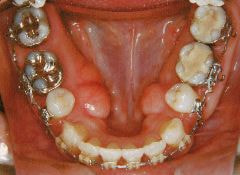

治療例1 (インプラント補綴+矯正)